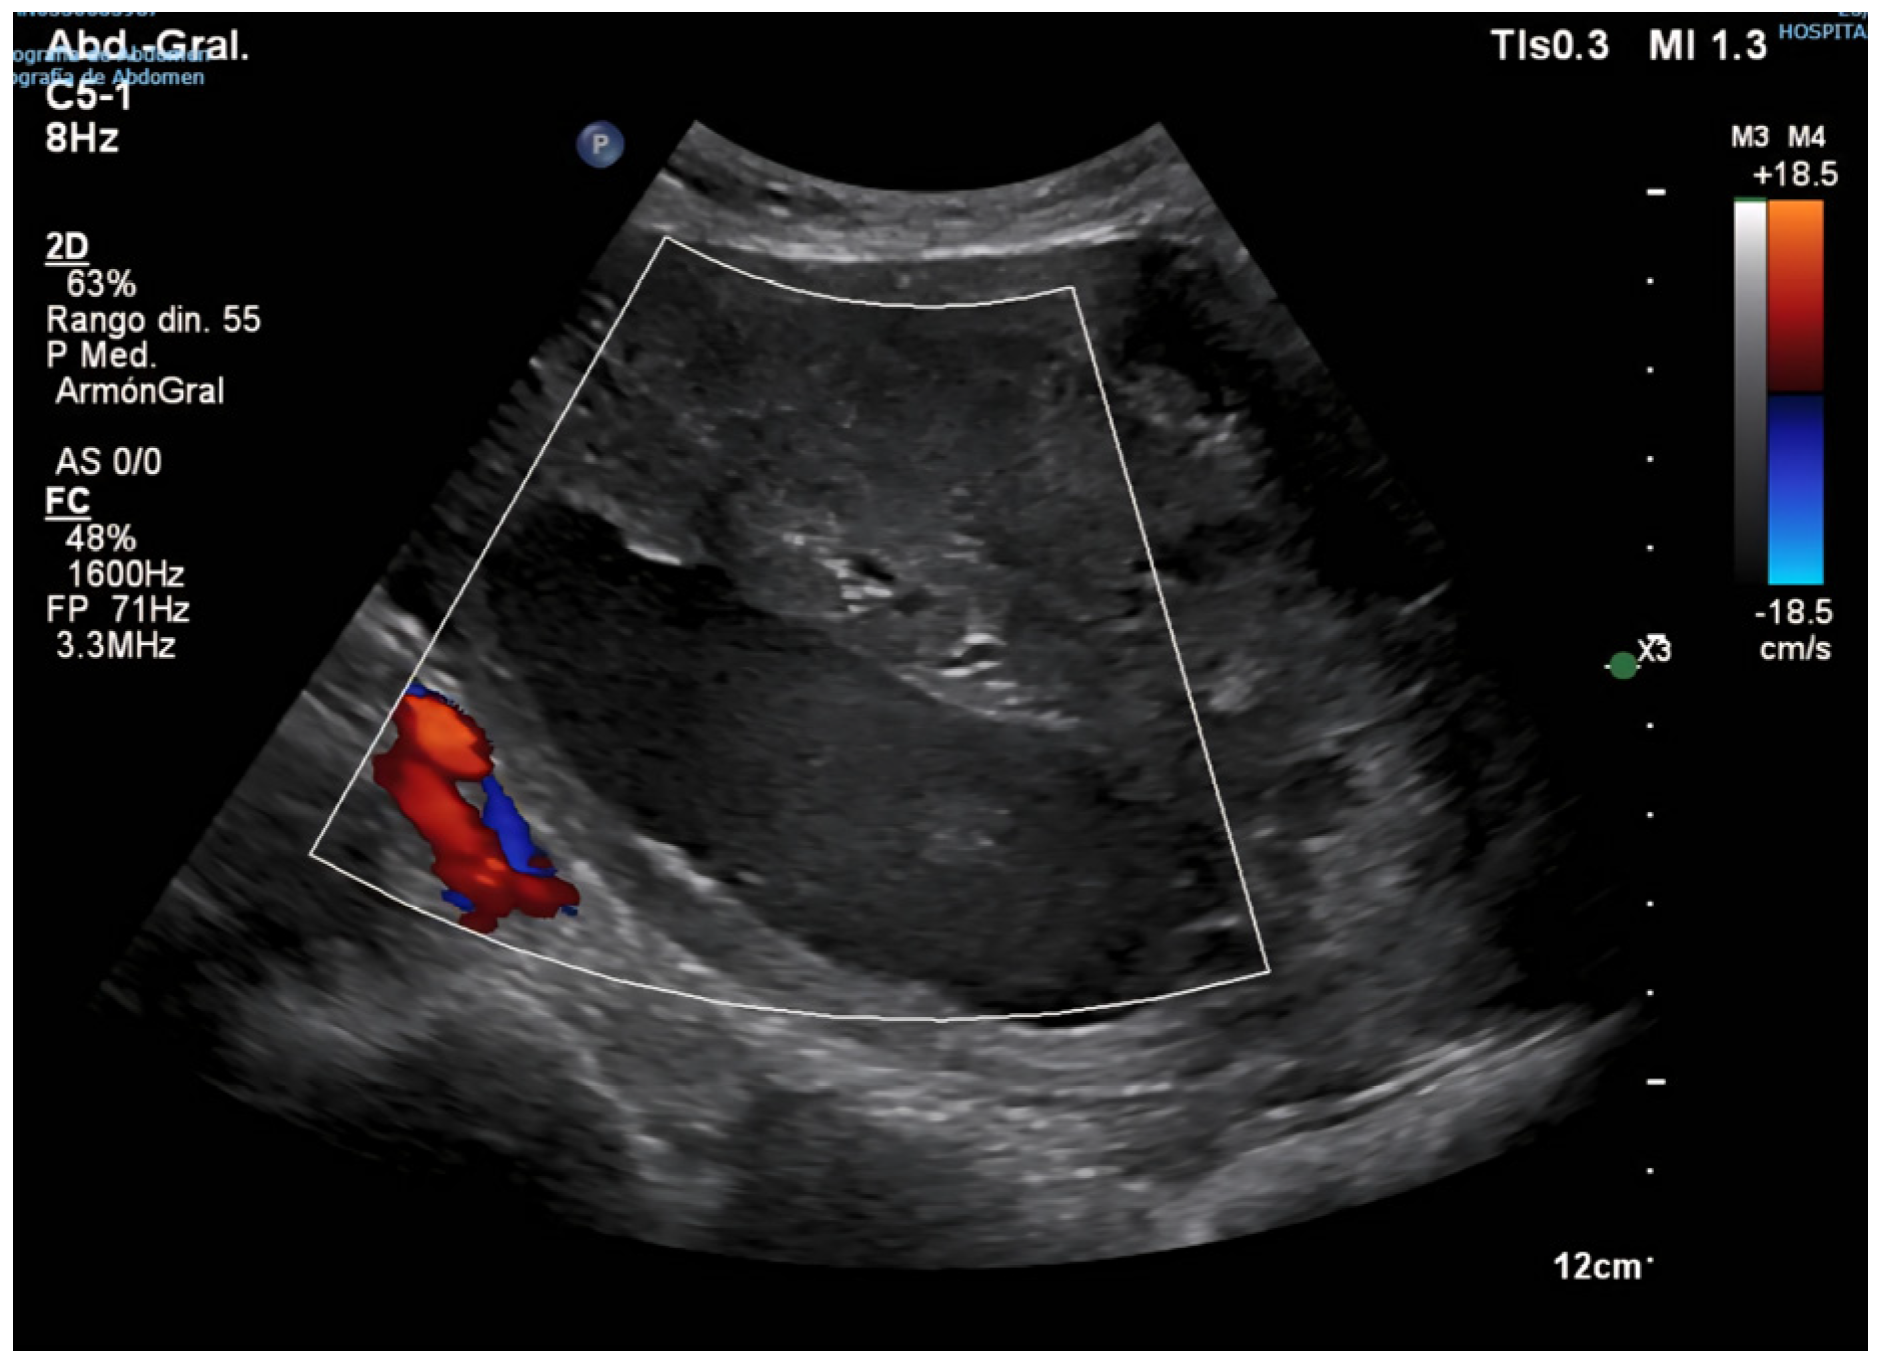

2. Case Presentation